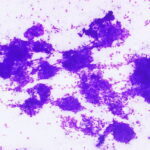

Cytopathology

Cytopathology Home

Picture Atlas